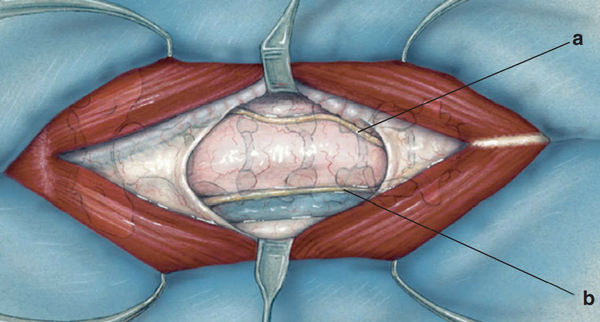

Sau khi rạch da và cắt dây chằng, có thể quan sát thấy cơ ức (a) tách sang hai bên, trong khi cơ ức-móng và cơ ức-giáp (b) nằm cạnh nhau ở vị trí trung tâm.

Cơ ức-móng và cơ ức-giáp có thể được tách dọc theo đường giữa. Nếu đường phân tách không rõ ràng, có thể dùng ngón tay ép nhẹ lên cơ nằm trên khí quản để làm lộ rõ đường giữa, giúp quá trình bóc tách trở nên dễ dàng hơn.

Khi cơ ức-móng và cơ ức-giáp được tách ra, khí quản sẽ lộ rõ, tạo điều kiện thuận lợi cho các bước tiếp theo trong phẫu thuật.